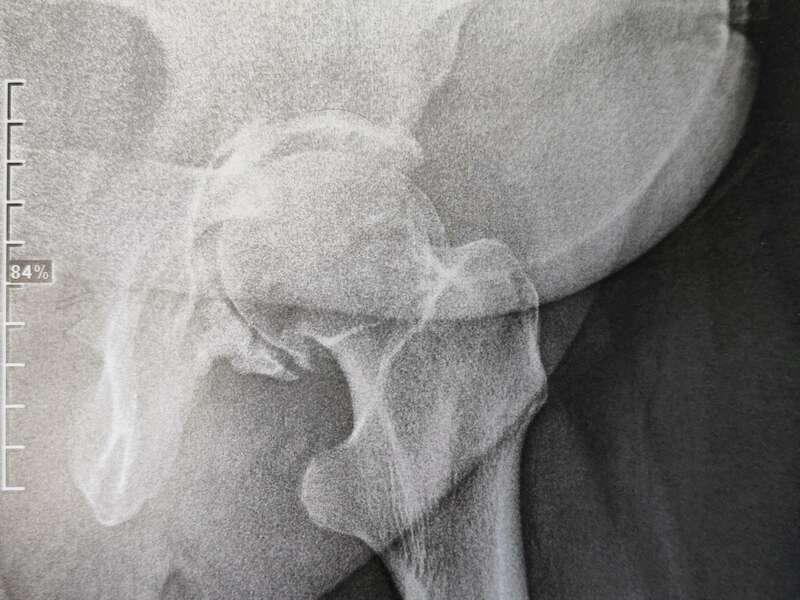

Elle sera confirmée par des examens radiologiques tels que des radiographies de hanche. En cas de doute diagnostic, afin d’éliminer un éventuel diagnostic différentiel, un scanner et/ou une IRM pourront être prescrits.

Qu’est-ce que l’arthrose de hanche ?

L’arthrose de hanche (aussi appelée coxarthrose) est une affection dégénérative, chronique, qui se manifeste par des douleurs et une diminution de la mobilité de l’articulation potentiellement handicapante. Elle peut évoluer lentement pendant une dizaine d’année ou devenir d’emblée invalidante.

L’arthrose désigne un processus d’usure du cartilage liée au vieillissement. Ce n’est pas une fatalité liée à l’âge. Elle cause des dommages irréversible du cartilage qui perd au fur et à mesure son rôle de surface de glissement et d’amortisseur. La pression sur l’os s’accroît à mesure que l’épaisseur cartilagineuse diminue. Des excroissances osseuses, appelées ostéophytes, des kystes osseux et des ulcérations cartilagineuses se forment progressivement.